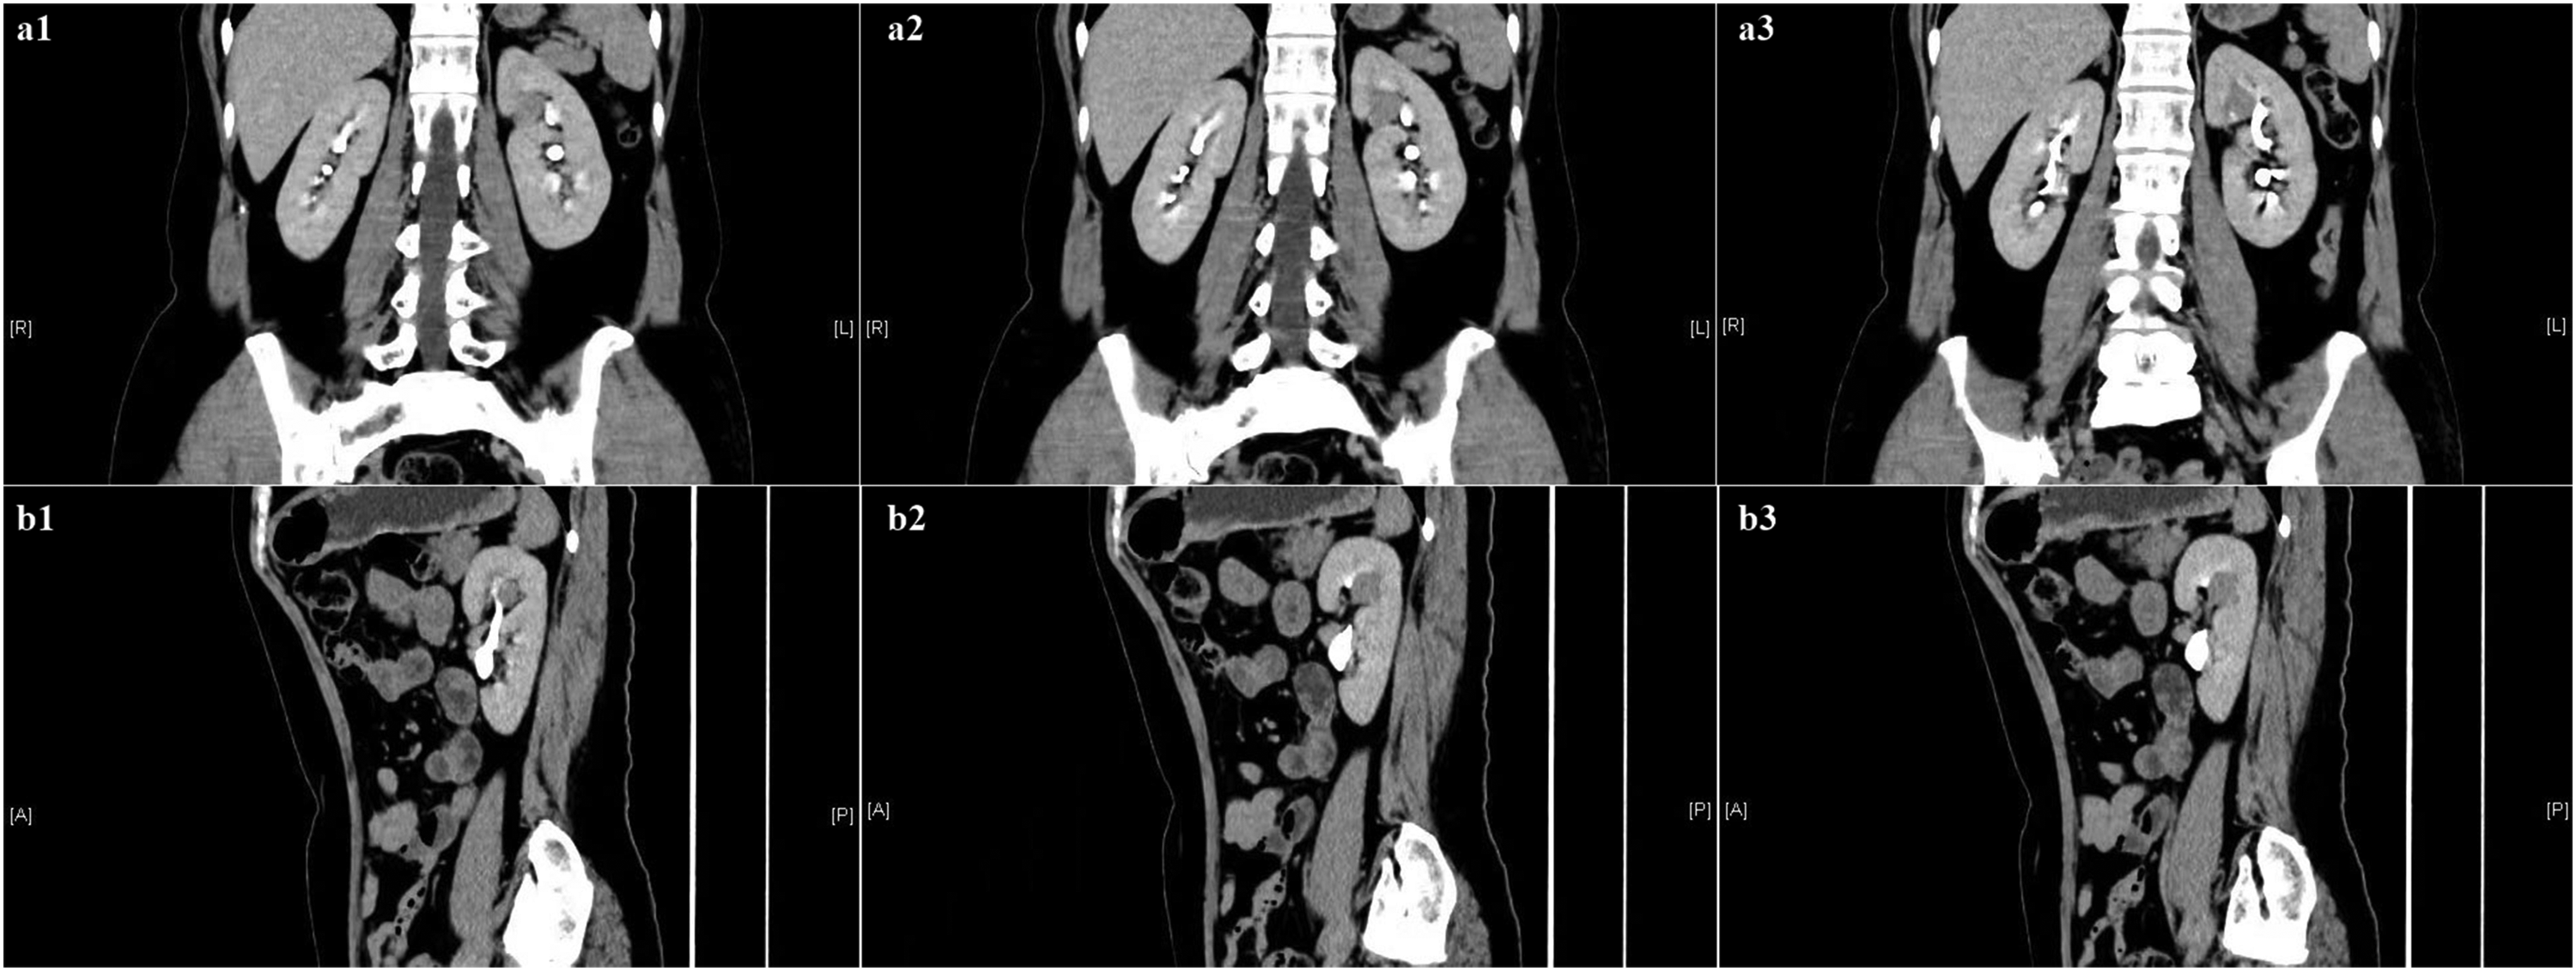

A 53-year-old woman presented with a 5-day history of intermittent abdominal pain, dizziness, and nausea. Physical examination revealed no remarkable abnormalities, and gross hematuria was not present. Computed tomography urography (CTU) revealed a small (approximately 19- × 16-mm) nodular shadow in the left kidney. The nodular shadow exhibited slightly lower density than the surrounding tissue as well as enhancement, with a portion protruding into the renal sinus region (Figure 1). Renal magnetic resonance imaging revealed round lesions exhibiting long T1 and short T2 signals in the left kidney (Figure 2). These lesions appeared hyperintense on diffusion-weighted imaging, showed an indistinct border, and measured approximately 20 mm in width (left–right), 18 mm in length (anterior–posterior), and 20 mm in height (superior–inferior). Based on the preoperative assessment, the diagnosis of left renal tumor was established, and laparoscopic partial nephrectomy was performed on 2 August 2022. The surgical procedure was conducted using retroperitoneal access. Intraoperatively, the perirenal fascia was incised, and the perirenal fat was isolated to expose the left kidney. Utilizing intraoperative laparoscopic ultrasound, a mass of approximately 2 cm in diameter located in the central region of the left kidney was identified. The tumor was surgically excised along with a portion of the kidney tissue. Upon gross examination, the specimen displayed a nodular consistency with dimensions of approximately 3.0 × 2.5 × 1.8 cm. The cut surface of the specimen exhibited vibrant colors and a soft texture. The pathological diagnosis of the left renal tumor was a well-differentiated NET. The tumor exhibited mitotic figures at a rate of 12 per 10 high-power fields, along with areas of necrosis. Notably, there was no involvement of the surgical stump. Immunohistochemistry analysis (Figure 3) demonstrated the following: pan cytokeratin (+), CD56 (+), synaptophysin (+), cytokeratin 7 (−), CD10 (−), vimentin (−), Wilms’ tumor protein 1 (−), p63 (−), Pax-8 (−), Ki-67 (+, about 5%), and somatostatin receptor 2 (3+).

Preoperative computed tomography urography images. The contrast-enhanced scans showed heterogeneous enhancement of the tumor in the (a1–3) coronal and (b1–3) sagittal images; no enhancement was observed in the central necrotic area.